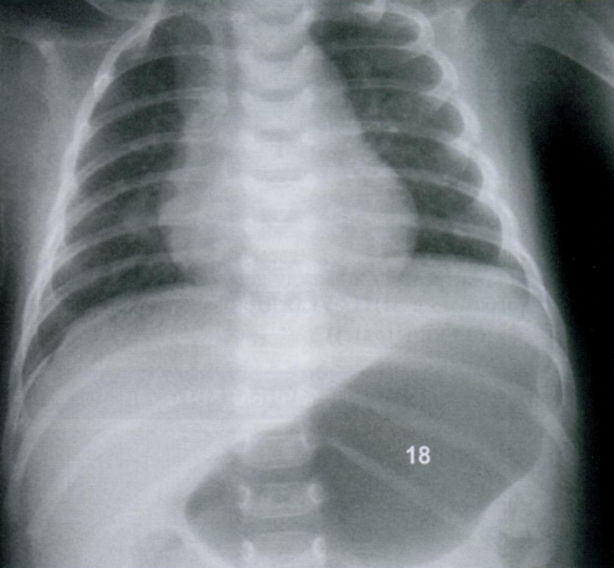

Данная рентгенография грудной клетки ребенка выполнена “на крике”. Что Вы можете отметить?

Оцените признаки наличия полнокровия/инфильтрации/аспирации мекония.

На данный момент обучения, возможно, Вы еще не знакомы с Rx-признаками пневмонии/аспирации мекония, однако визуально посмотрите на снимок и отметитьте некоторые черты, которые притягивают внимание.

Какие-то инфильтраты и полнокровие точно есть. И тут Вы начнете думать: почему? Пациент явно ребёнок. Аспирация? Пневмония?

Мы смотрим снимке ВСЕГДА в контексте клинической картины, но тут просто поразмыслим.

Ниже представлен снимок того же ребенка, который перестал плакать и лаборант успел выполнить повторный снимок.

Мы видим нормальную рентгенограмму грудной клетки (чистые легочные поля), и аэрофагию (18) - воздух в желудке, проглоченный во время плача.

Мораль: необходимо определить в какой фазе дыхания был выполнен снимок + ВСЕГДА иметь клинический контекст.